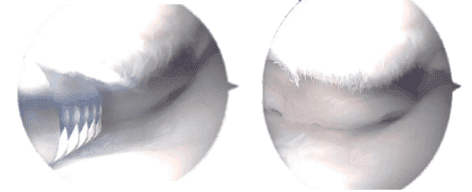

Intraoperative Arthroscopic images taken during operation

Final pictures taken during operation

The knee scope was then inserted through a lateral working aperture in the left knee. A knee examination revealed patellofemoral arthritis, particularly in the distal medial patellar joint.

The trochlea had OA grade 1 to 2 changes, and the medial inferior patellar component had OA grade 3 to 4 changes. Chondroplasty of the inferomedial patellar aspect was combined with a medial femoral gutter synovectomy.